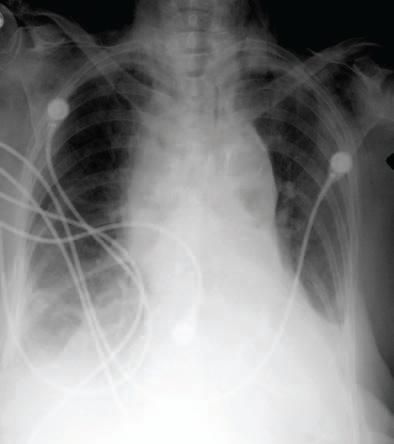

On November 7, the patient was noted to be more lethargic, but the vital signs remained stable and there was no evidence of respiratory distress. The patient was evaluated by thoracic surgery. A portable chest radiograph showed widening of the superior mediastinum with small bilateral pleural effusions (Figure 2).

Figure 2 - A chest radiographobtained November 7, 2005,shows that the transverse diameterof the superior mediastinumhas increased in comparisonto what was visualized inthe previous radiograph.